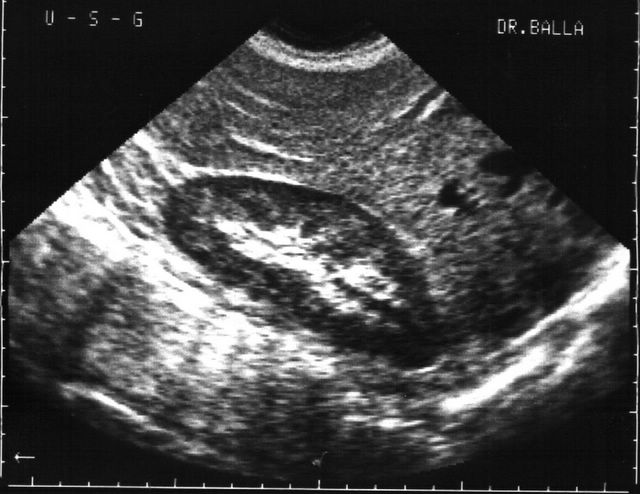

Лучевая диагностика мочекаменной болезни включает в себя рентгеновское обследование и компьютерную томографию. Также одним из основных методов определения камней в почках остаётся УЗИ. С его помощью уролог может определить количество конкрементов, их размеры, форму и локализацию. Этот способ применяется, как альтернатива, если нет возможности провести компьютерную томографию (КТ).

Обратите внимание! Единственный недостаток УЗИ состоит в том, что при определённой локализации камней в мочеточниках их практически невозможно рассмотреть. Поэтому здесь эффективнее проводить внутривенную пиелографию или КТ.

УЗИ почек — основной метод диагностики, позволяющий определить наличие, размер и расположение камней. Дополнительно могут быть назначены компьютерная томография (КТ) или экскреторная урография. В заключение понимание симптомов МКБ способствует своевременному обращению за медицинской помощью.

Диагностика камней мочевого пузыря. Чтобы обследовать мочевой пузырь и обнаружить камни, а также оценить их размеры и точную локализацию, обычно достаточно сделать УЗИ при наполненном мочевом пузыре. Другим способом достичь этого является цистоскопия — эндоскопическое исследование полости пузыря.